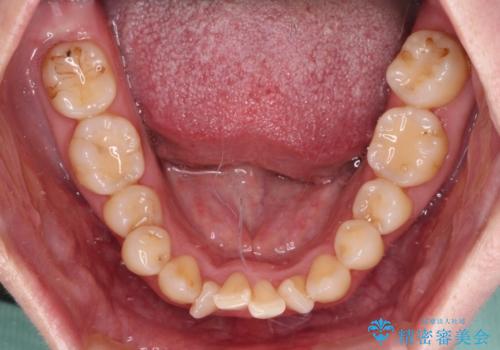

舌の突出癖が強く、治療途中で上下前歯が乖離した開咬となってしまいました。

舌のトレーニングで開咬は改善できますが、なかなかトレーニングが進まず、治療期間は想定よりも長期化してしまいました。